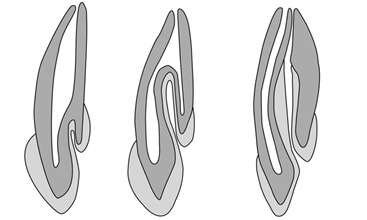

Інвагінація зуба (dens invaginatus) – вада розвитку (так звана зуб в зубі) при якій відбувається вдавлення зубної емалі до середини коронки зуба. Найчастіше зустрічається в латеральних різцях верхньої щелепи та досить часто, зустрічається в обох білатеральних різцях. Клініцисти найчастіше використовують класифікацію Oehlers, згідно якої виділяють три типи:

I. Інвагінація досягає цементно-емалевого з’єднання.

II. Інвагінація виходить за межі цементно-емалевого з’єднання в ділянку кореня і там закінчується.

III. Інвагінація не має сполучення з основним каналом та має окремий апікальний отвір (див. схема 1).